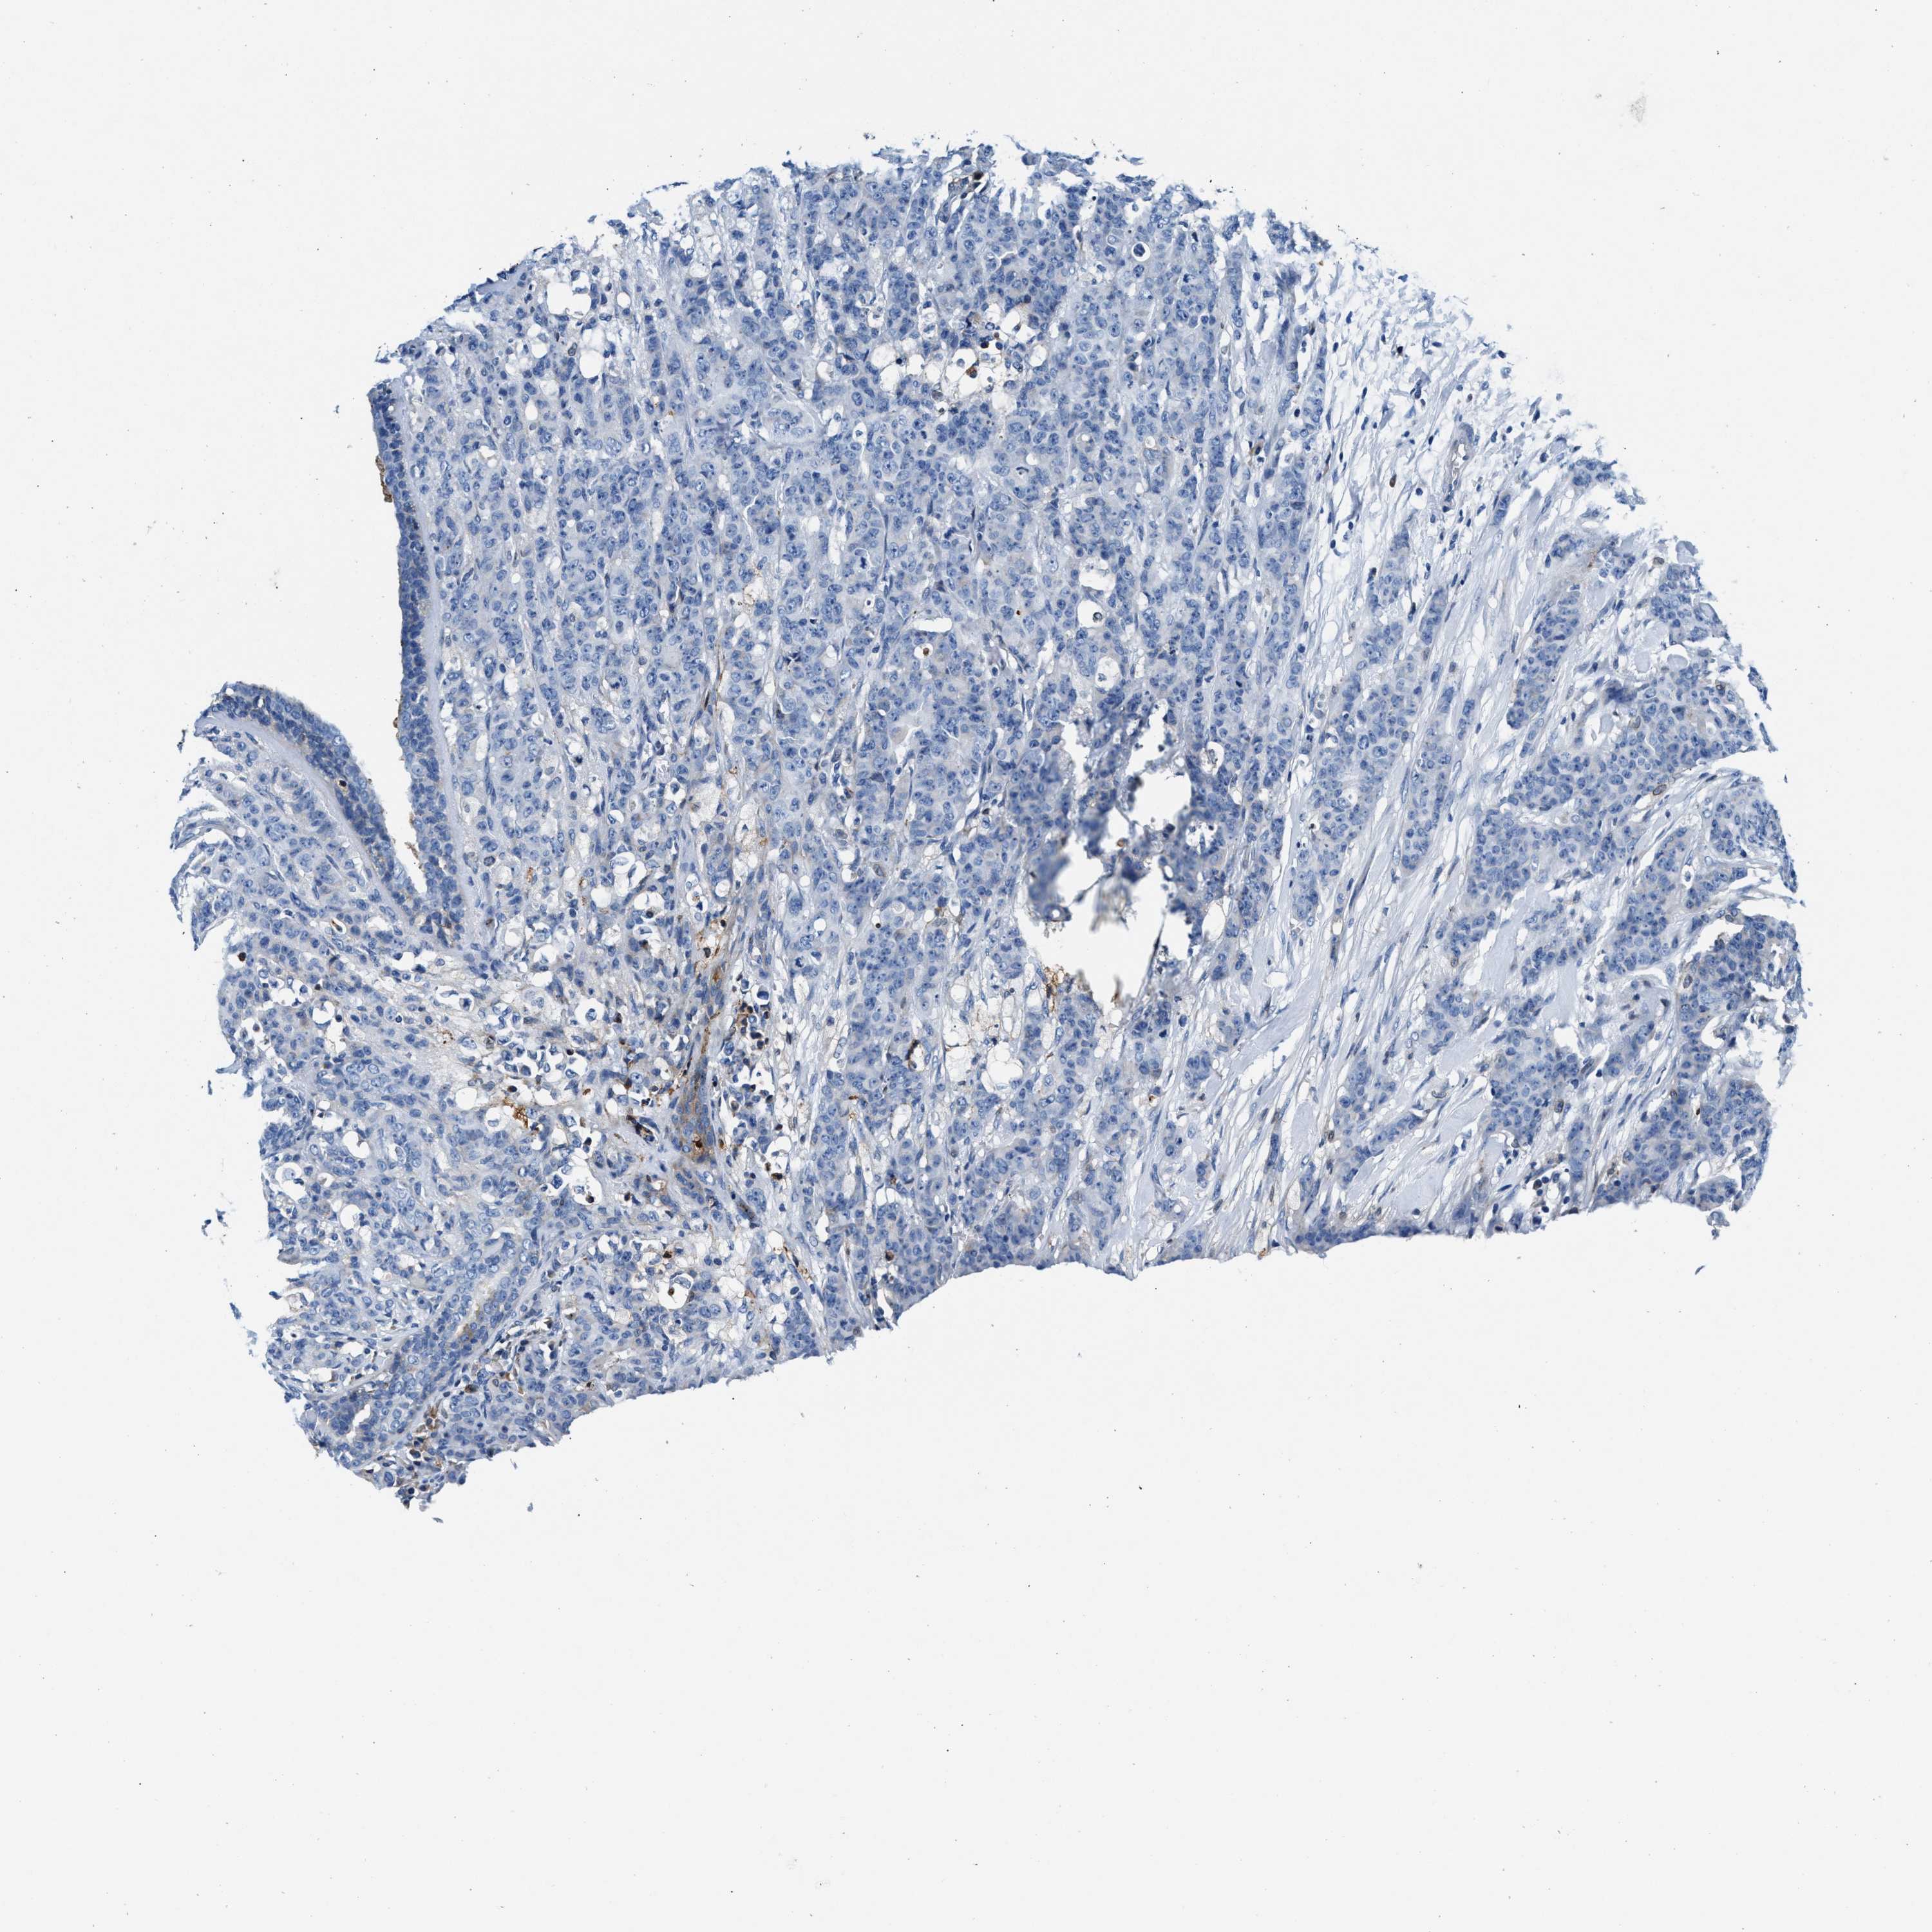

CANCER BREAST CANCER Show tissue menu

BRCA TCGA BRCA VALIDATION PROTEIN EXPRESSION